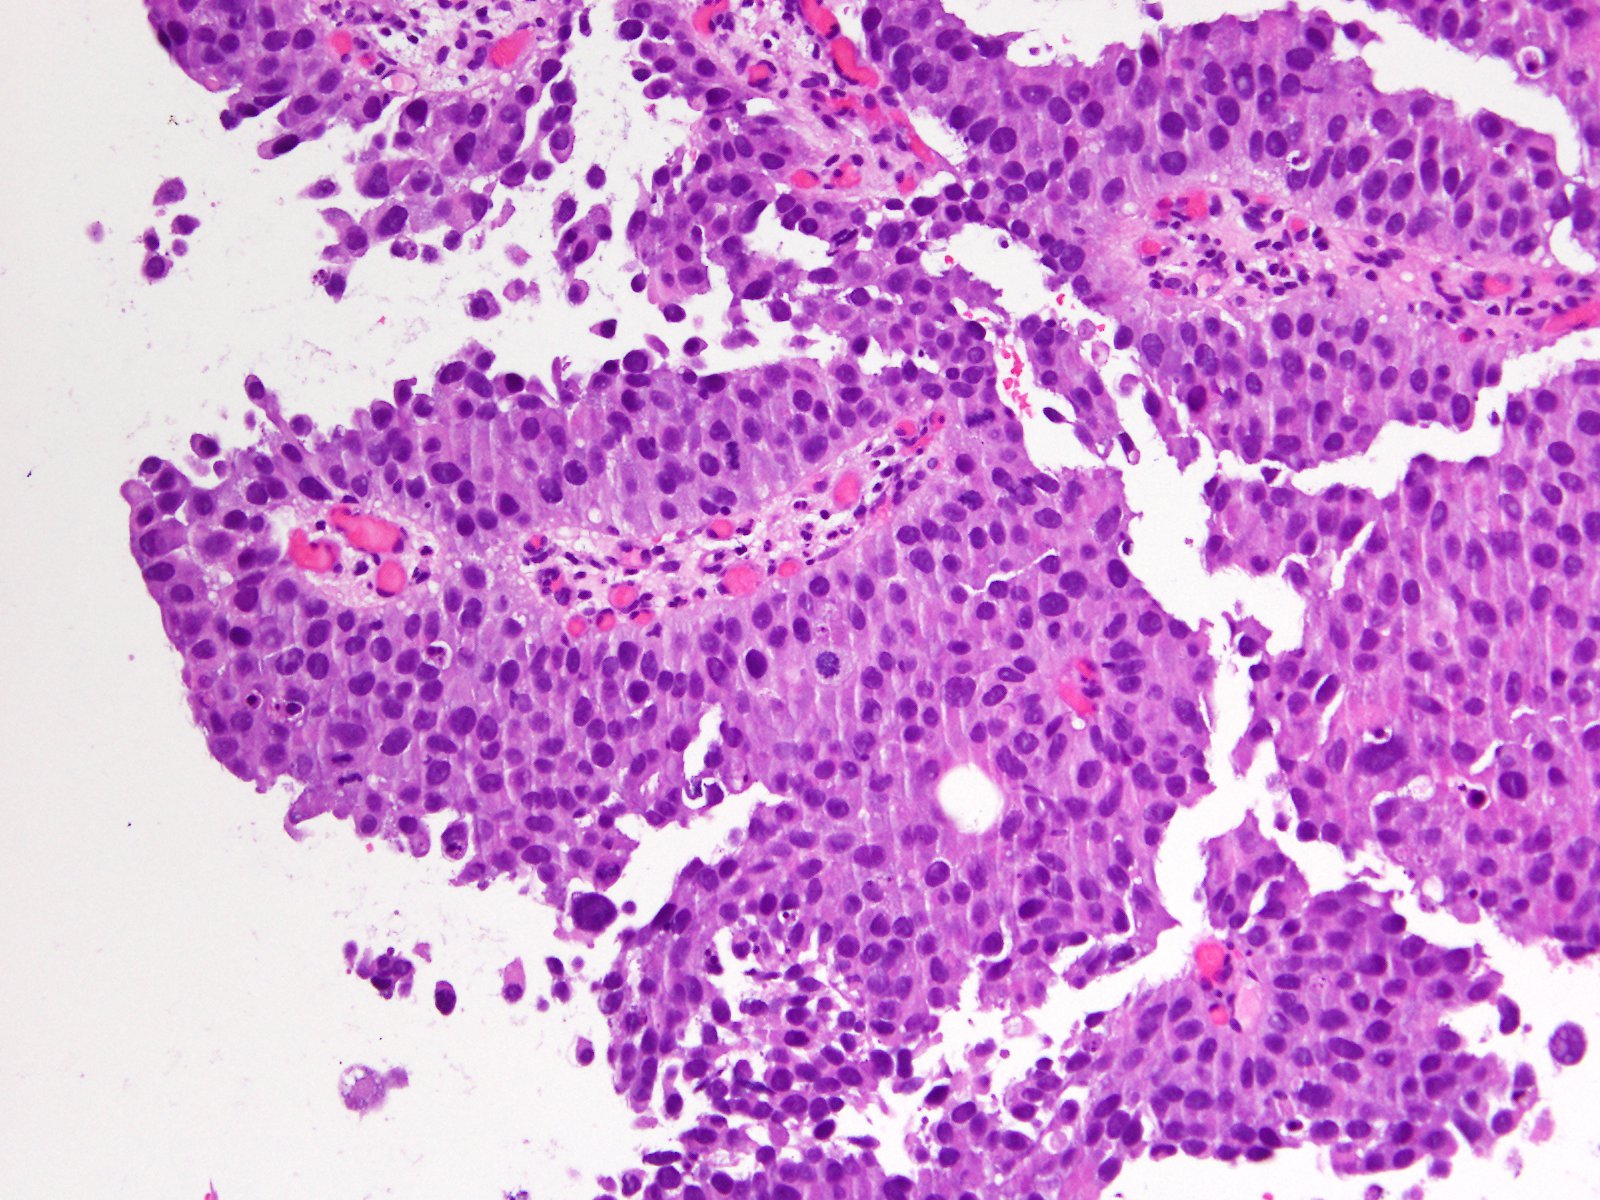

Bladder Papillary Lesions

Case ID: 363